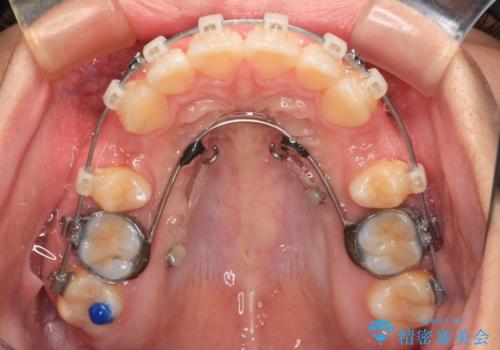

- 矯正装置

- クリアブラケット

また、上顎歯列が下顎に対して前方位に位置していたため、補助装置を用いて上顎歯列を後方に移動させ、より積極的に口元を下げるようにしました。

上下正中位置を改善するため、左下はイレギュラーに第二小臼歯を抜歯しました。そのため治療期間の長期化が予想されましたが、2年半ほどで期待通りの歯列に仕上げることができました。